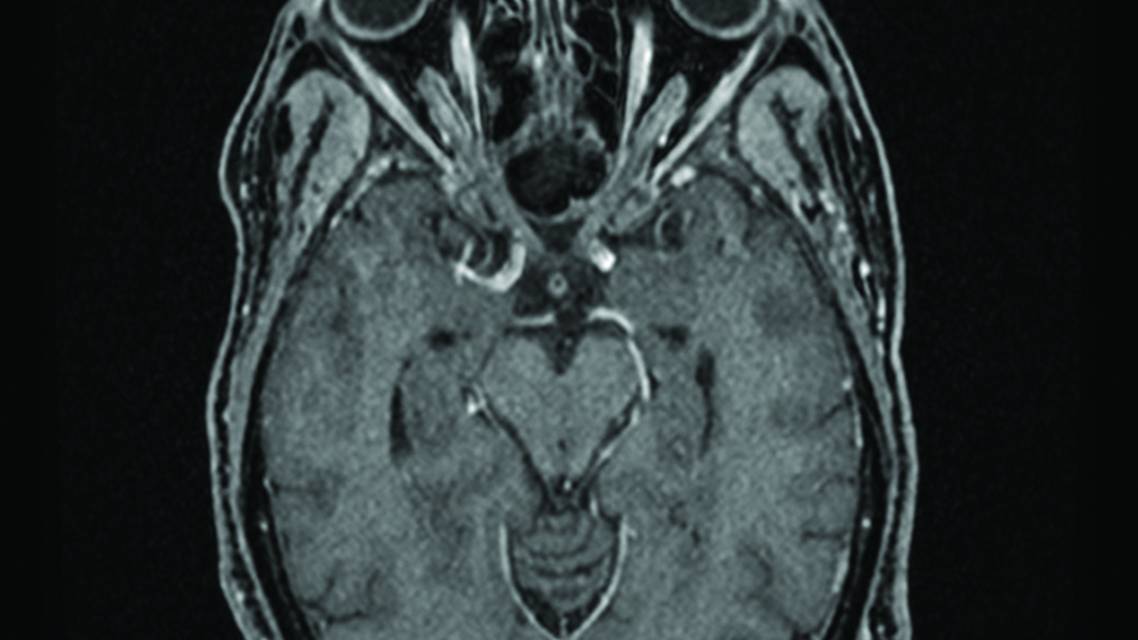

Brain MRI and magnetic resonance venography with and without contrast showed no acute intracranial findings, normal ventricles, no frank leptomeningeal disease, and no venous sinus thrombosis. Although initially read as having no areas of abnormal contrast enhancement, subsequent review of imaging studies at a multidisciplinary case conference revealed subtle asymmetry in cranial nerves II and VIII, concerning for direct nerve involvement (Figure 2, A and B). Total spine MRI was not obtained due to no concerning symptoms for spinal cord or cauda equina involvement, although in hindsight this would be standard evaluation given concerns for leptomeningeal disease.

Four months after discharge, ZE had complete resolution of all symptoms. Laboratory studies at that time showed a WBC count of 13.9 K/mm3, absolute lymphocyte count of 9.6, radiographic resolution of the previous MRI findings (Figure 2, C–E), and resolution of papilledema. Optical coherence tomography 5 months after discharge demonstrated interval resolution of RNFL thickening (left average RNFL thickness 91 µm, right average RNFL thickness 89 µm) with mild thinning of the ganglion cell layer. This improvement was stable at further follow-up 8 months after discharge.

Figure 2. Subtle asymmetric enhancement within the internal auditory canals involving the cranial nerve VII/VIII complexes on postcontrast volumetric interpolated breath-hold examination sequence MRI (A). Asymmetric enhancement of the optic nerves on postcontrast volumetric interpolated breath-hold examination sequence MRI (B). Interval MRI resolution of contrast enhancement involving the optic nerves (C, D) and internal auditory canals (E).